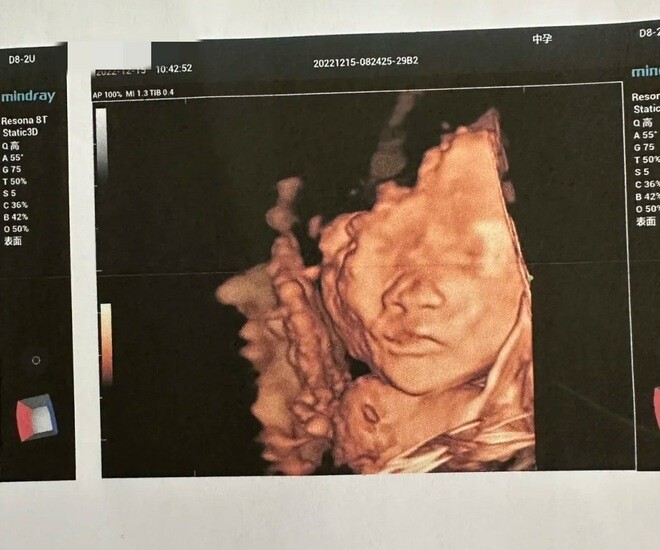

Đến ngày siêu âm ở tuần thứ 22, họ lựa chọn một bệnh viện cho phép người cha vào phòng siêu âm. Bác sĩ thoa gel lên bụng Huihui và di chuyển đầu dò. Thai nhi khá “hợp tác”, lần lượt hiện lên trên màn hình từ đôi bàn chân nhỏ, phần mông, lưng, sau đó là phía sau đầu và cuối cùng là khuôn mặt.

Đúng lúc đó, đứa trẻ đột nhiên cười toe toét.

Người chồng càng vui mừng "Nhìn kìa, em bé thực sự đang cười. Có vẻ như thai giáo trước khi sinh rất tốt đó. Đứa bé biết tôi là bố của nó".

Tuy nhiên, trái với sự hân hoan của hai vợ chồng, bác sĩ siêu âm – một người đã có nhiều năm kinh nghiệm – lại trầm giọng nhận xét rằng hình ảnh thai nhi cười không hẳn là dấu hiệu tích cực. Bác sĩ hỏi liệu thai kỳ này có được chuẩn bị kỹ lưỡng và người mẹ có bổ sung axit folic đầy đủ trong giai đoạn đầu hay không.

Sau khi xem xét kỹ hình ảnh siêu âm, bác sĩ cho biết thai nhi có dấu hiệu sứt môi – tình trạng môi trên không khép kín, khiến khi cười trông như đang “nở nụ cười bất thường”.

Bác sĩ giải thích rằng sứt môi là dị tật bẩm sinh do nhiều yếu tố gây ra, trong đó thiếu axit folic trong thai kỳ là một nguyên nhân quan trọng. Với y học hiện đại, các trường hợp nhẹ có thể phẫu thuật chỉnh hình, nhưng những ca nặng có thể ảnh hưởng đến việc ăn uống, phát âm và cả tâm lý của trẻ khi lớn lên.

Ảnh minh họa